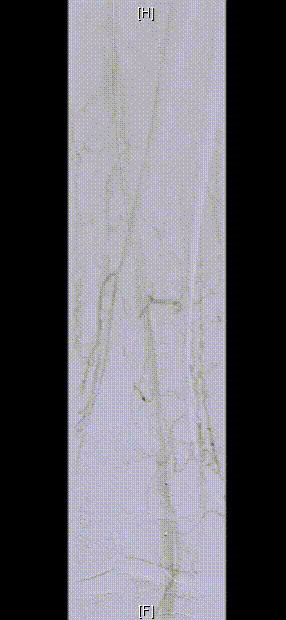

图为:股腘动脉DAART+区域性DES 最终造影

图为:2023年11月 2年后复查

2年后(2023-11)复查

下肢动脉CTA提示左股腘动脉通畅,DES区域未见内膜增生管腔丢失表现